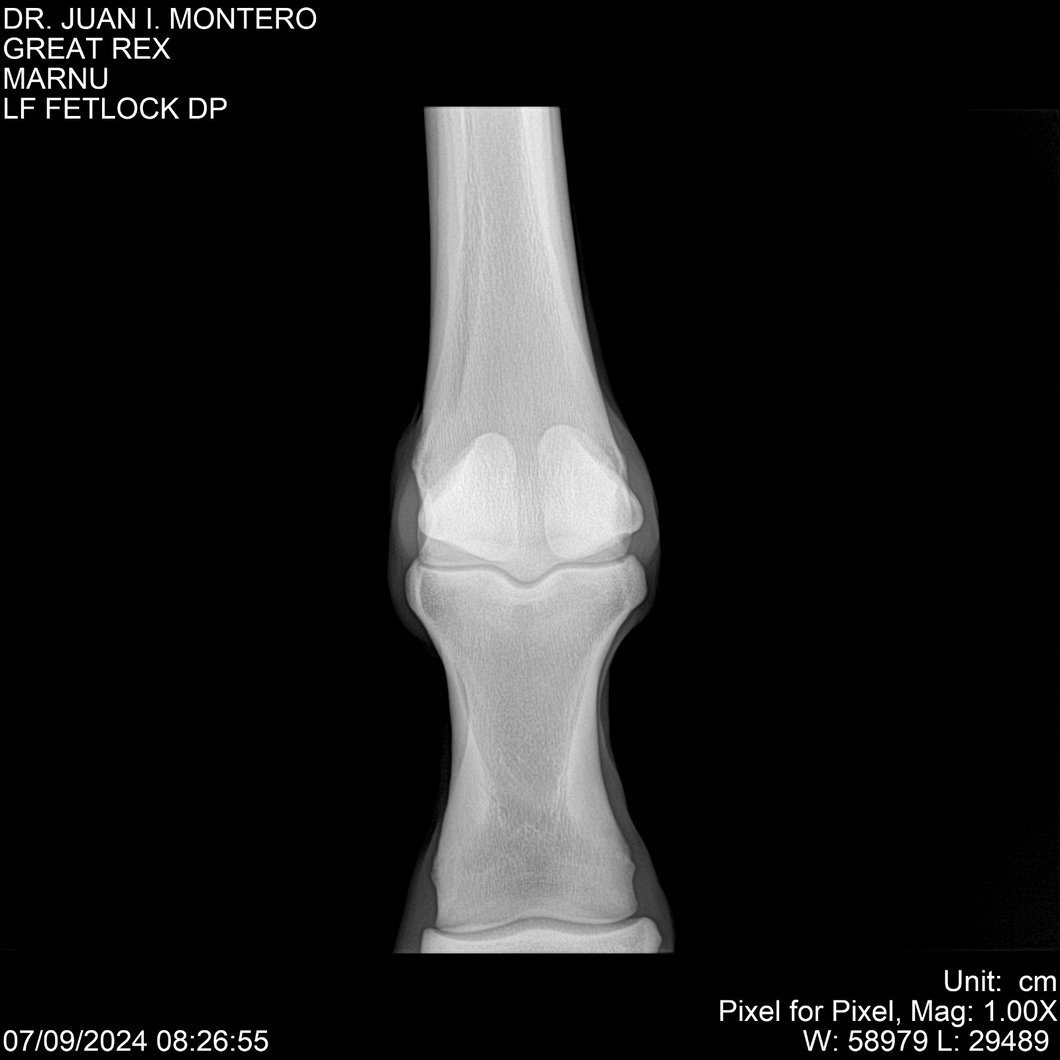

LOTE 4, GREAT REX Lote Anterior Volver al remate Lote Siguiente Ficha Contacto Montevideo - Ficha del Lote Identificador: #282518 Categoría: Yeguarizos Montevideo - 66 Visualizaciones ClicData Contacto Empresa: Abelenda N. R., Walter Hugo Nombre*: Teléfono* : E-mail* : Mensaje Enviar Registrese gratis Este contenido Exclusivo está disponible sólo para usuarios registrados Ingresar